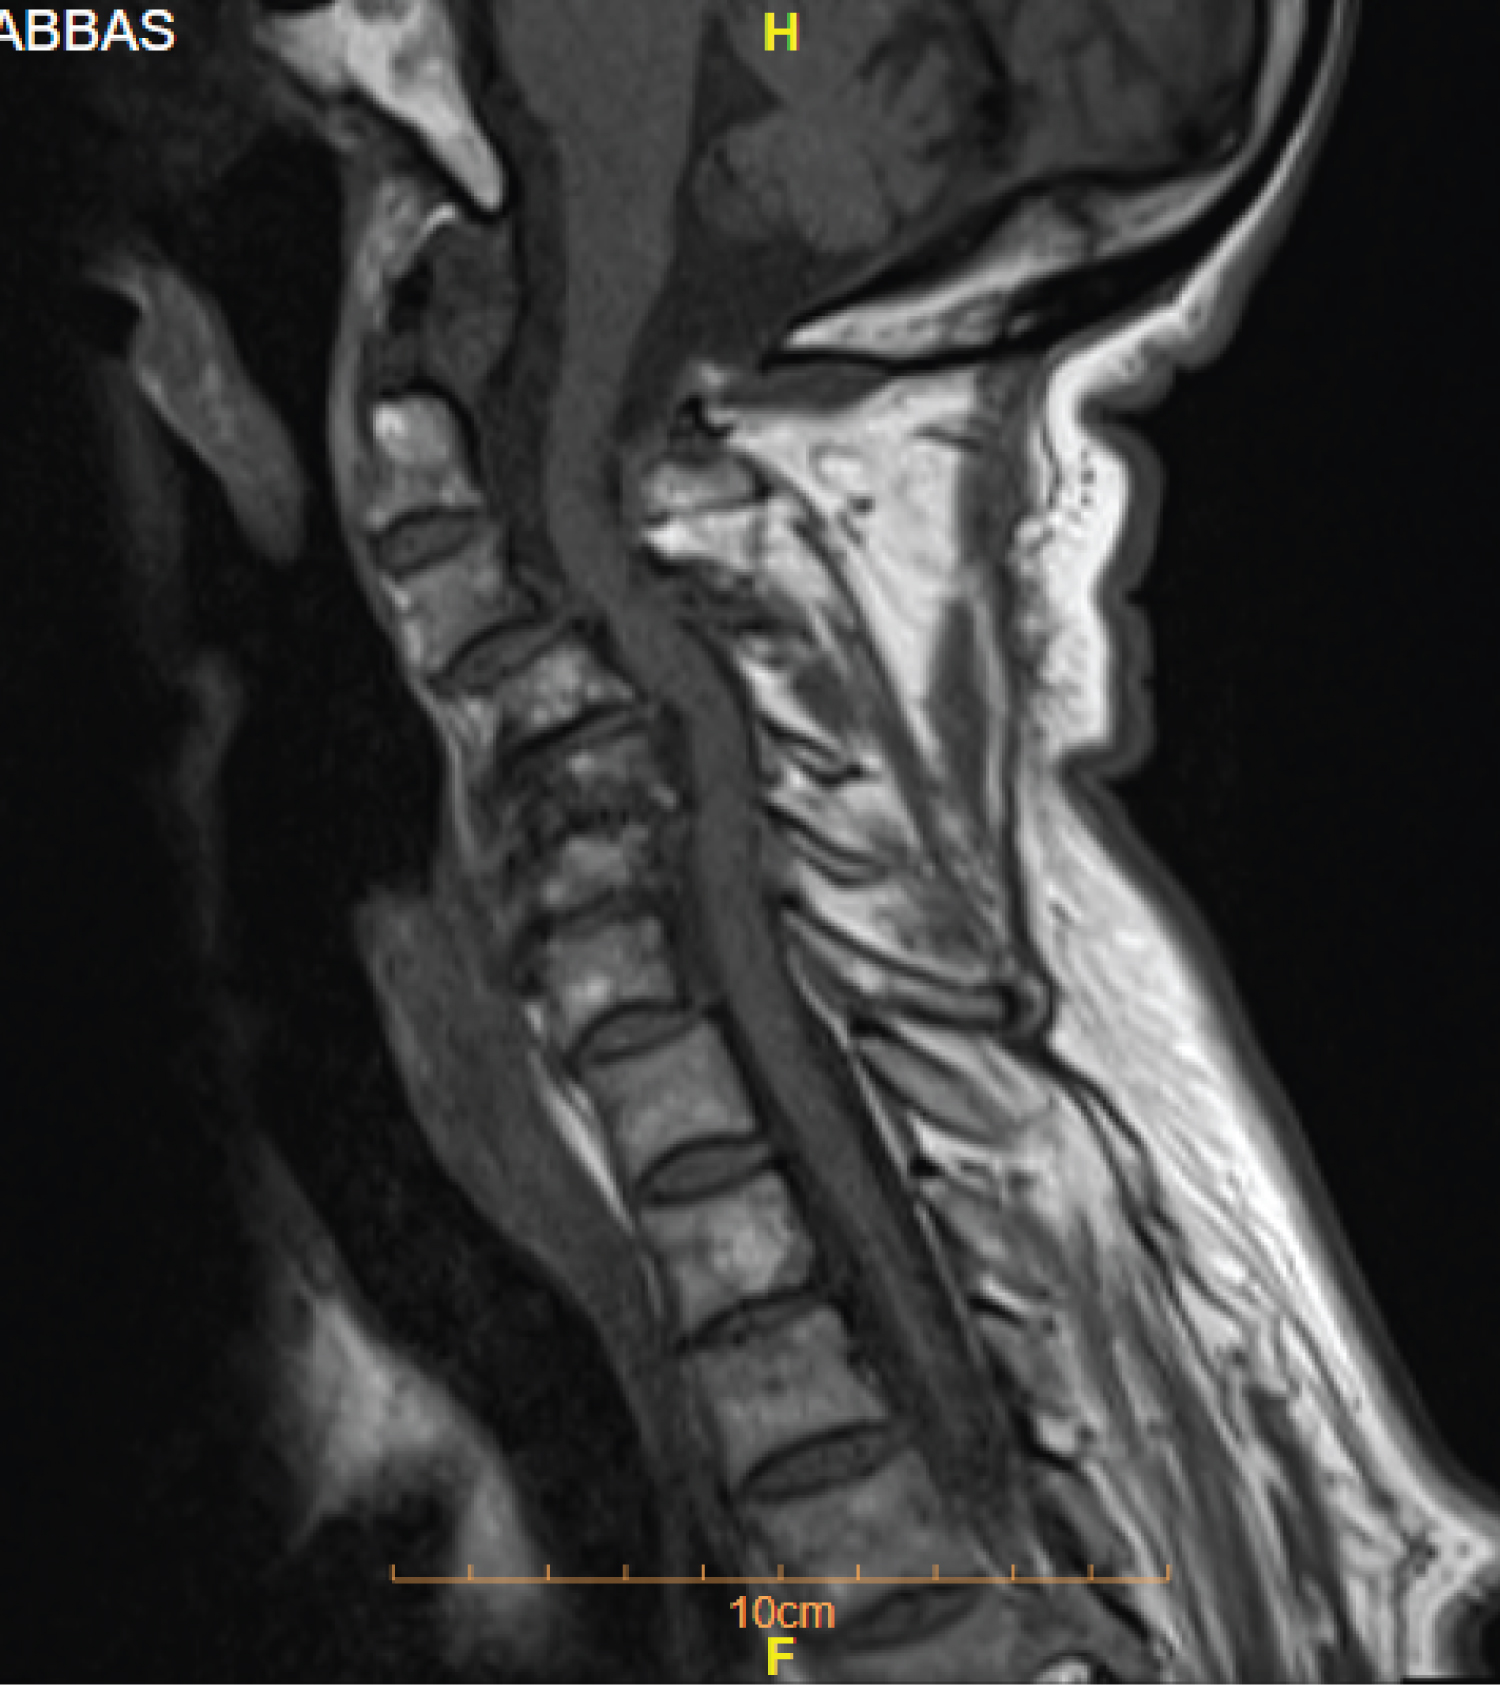

Magnetic Resonance Imaging (MRI) of the cervical spine showed stenosis with cord compression from C3 to C7 levels (Figure 1). Sagittal computed tomography image of the cervical spine showing ossified yellow ligament from c4 to c7 (Figure 2 and Figure 3).

Figure 1: Sagittal T1 weighted MR image of the cervical spine showing a narrowed spinal canal due to a low signal intensity mass anterior to the posterior elements with cord oedema at C4 - C7 levels.

View Figure 1